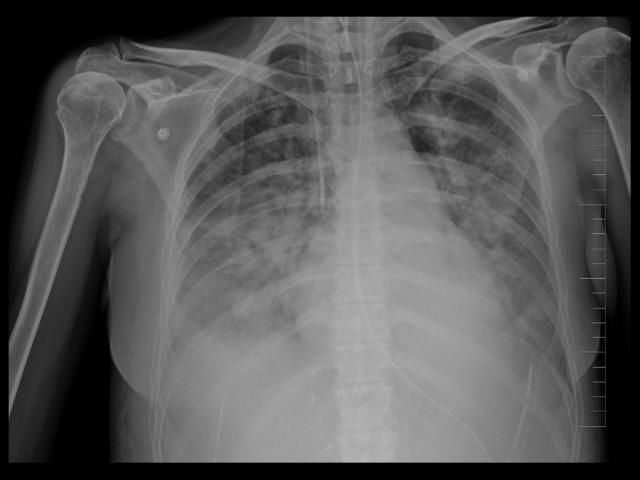

BACKGROUND Takotsubo cardiomyopathy (TTC) is a cardiac syndrome characterized by transient left ventricle (LV) dysfunction, typically showing apical ballooning due to apical akinesis with preserved basal segment contractility. The inverted form is very uncommon and is characterized by basal segment hypokinesis or akinesis and normal LV apical segment contractility. CASE REPORT We describe the case of a 49-year-old woman who developed inverted TTC after orthotopic liver transplantation. On day 1 (D1), dyspnea and oliguria suddenly appeared. A chest X-ray showed pulmonary edema, and echocardiography showed severe systolic LV dysfunction with an estimated ejection fraction of approximately 25% and akinesis of basal and midventricular LV segments, normal apical segment contractility, and mild mitral regurgitation. Elevated troponin T, creatine kinase-MB, and N-terminal pro B-type natriuretic peptide were found in the blood sample. Suspected inverted takotsubo cardiomyopathy was confirmed by left ventriculography, with normal apical part motion, akinesis in the other LV parts, and negative coronary angiography. The echocardiographic findings returned to normal on D14, and the patient was discharged from the hospital on D19 with normal LV motion and an ejection fraction of 65%. The transplanted liver function was excellent. CONCLUSIONS Organ transplantation is connected with a great emotional stress because the patient's life depends on the death of another person. Therefore, we have to think about the possibility of stress cardiomyopathy even after liver transplantation, because early diagnosis and treatment can be life-saving for the patient. To our knowledge, this is the first described case of inverted takotsubo cardiomyopathy after liver transplantation.

背景 应激性心肌病(TTC)是一种以短暂性左心室(LV)功能障碍为特征的心脏综合征,典型表现为心尖运动消失导致心尖部膨出,而基底节段收缩功能保留。倒置型非常罕见,其特征是基底节段运动减弱或消失,左心室心尖段收缩功能正常。病例报告 我们描述了一例49岁女性在原位肝移植后发生倒置型TTC的病例。在第1天(D1),突然出现呼吸困难和少尿。胸部X线显示肺水肿,超声心动图显示严重的左心室收缩功能障碍,估计射血分数约为25%,左心室基底和中间段运动消失,心尖段收缩功能正常,伴有轻度二尖瓣反流。血液样本中发现肌钙蛋白T、肌酸激酶-MB和N末端B型利钠肽前体升高。左心室造影证实为疑似倒置型应激性心肌病,心尖部运动正常,左心室其他部位运动消失,冠状动脉造影阴性。超声心动图检查结果在第14天恢复正常,患者于第19天出院,左心室运动正常,射血分数为65%。移植肝脏功能良好。结论 器官移植伴随着巨大的情感压力,因为患者的生命依赖于另一个人的死亡。因此,即使在肝移植后,我们也必须考虑应激性心肌病的可能性,因为早期诊断和治疗可能挽救患者生命。据我们所知,这是首例报道的肝移植后倒置型应激性心肌病病例。